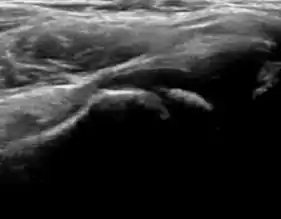

During childhood, ultrasound is a quick method to assess hip pain and quite often may be used to avoid use of irradiating techniques, such as radiography or CT. Ultrasound allows evaluation of joint effusion, synovial thickening and neovascularity, the bone/cartilage contour, and the femoral head-neck alignment. Although sonography is extremely sensitive in detecting increased synovial fluid, it is nonspecific and cannot be used with accuracy to determine the type of fluid. Transient synovitis of the hip, despite being the most frequent cause of pain in children between 3 and 10 years, remains a diagnosis of exclusion. It usually shows anechoic fluid, but echogenic fluid can also be found. The effusion is considered pathologic when it is measured at >2 mm in thickness. The differential diagnosis is wide, including osteomyelitis, septic arthritis, primary or metastatic lesions, LCPD, and SCFE. Discrimination from septic arthritis is challenging, often requiring joint aspiration. In septic arthritis, US is able to demonstrate a hip joint effusion, synovial thickening, and cartilage damage, although the appearances are nonspecific.[1]

A step between the head and the physis can be detected in children with SCFE, while abnormalities in the femoral head contour may suggest the presence of LCPD. In both cases, radiographs are mandatory to confirm diagnosis and severity (Figure 12).[1]

Figure 12:

In adults, the most common application for US is to detect tendon or muscle injuries, effusion or synovitis within the hip joint or its adjacent bursae. Joint effusions may be due to many intra-articular processes and this may need another imaging technique to achieve a specific diagnosis.[1]